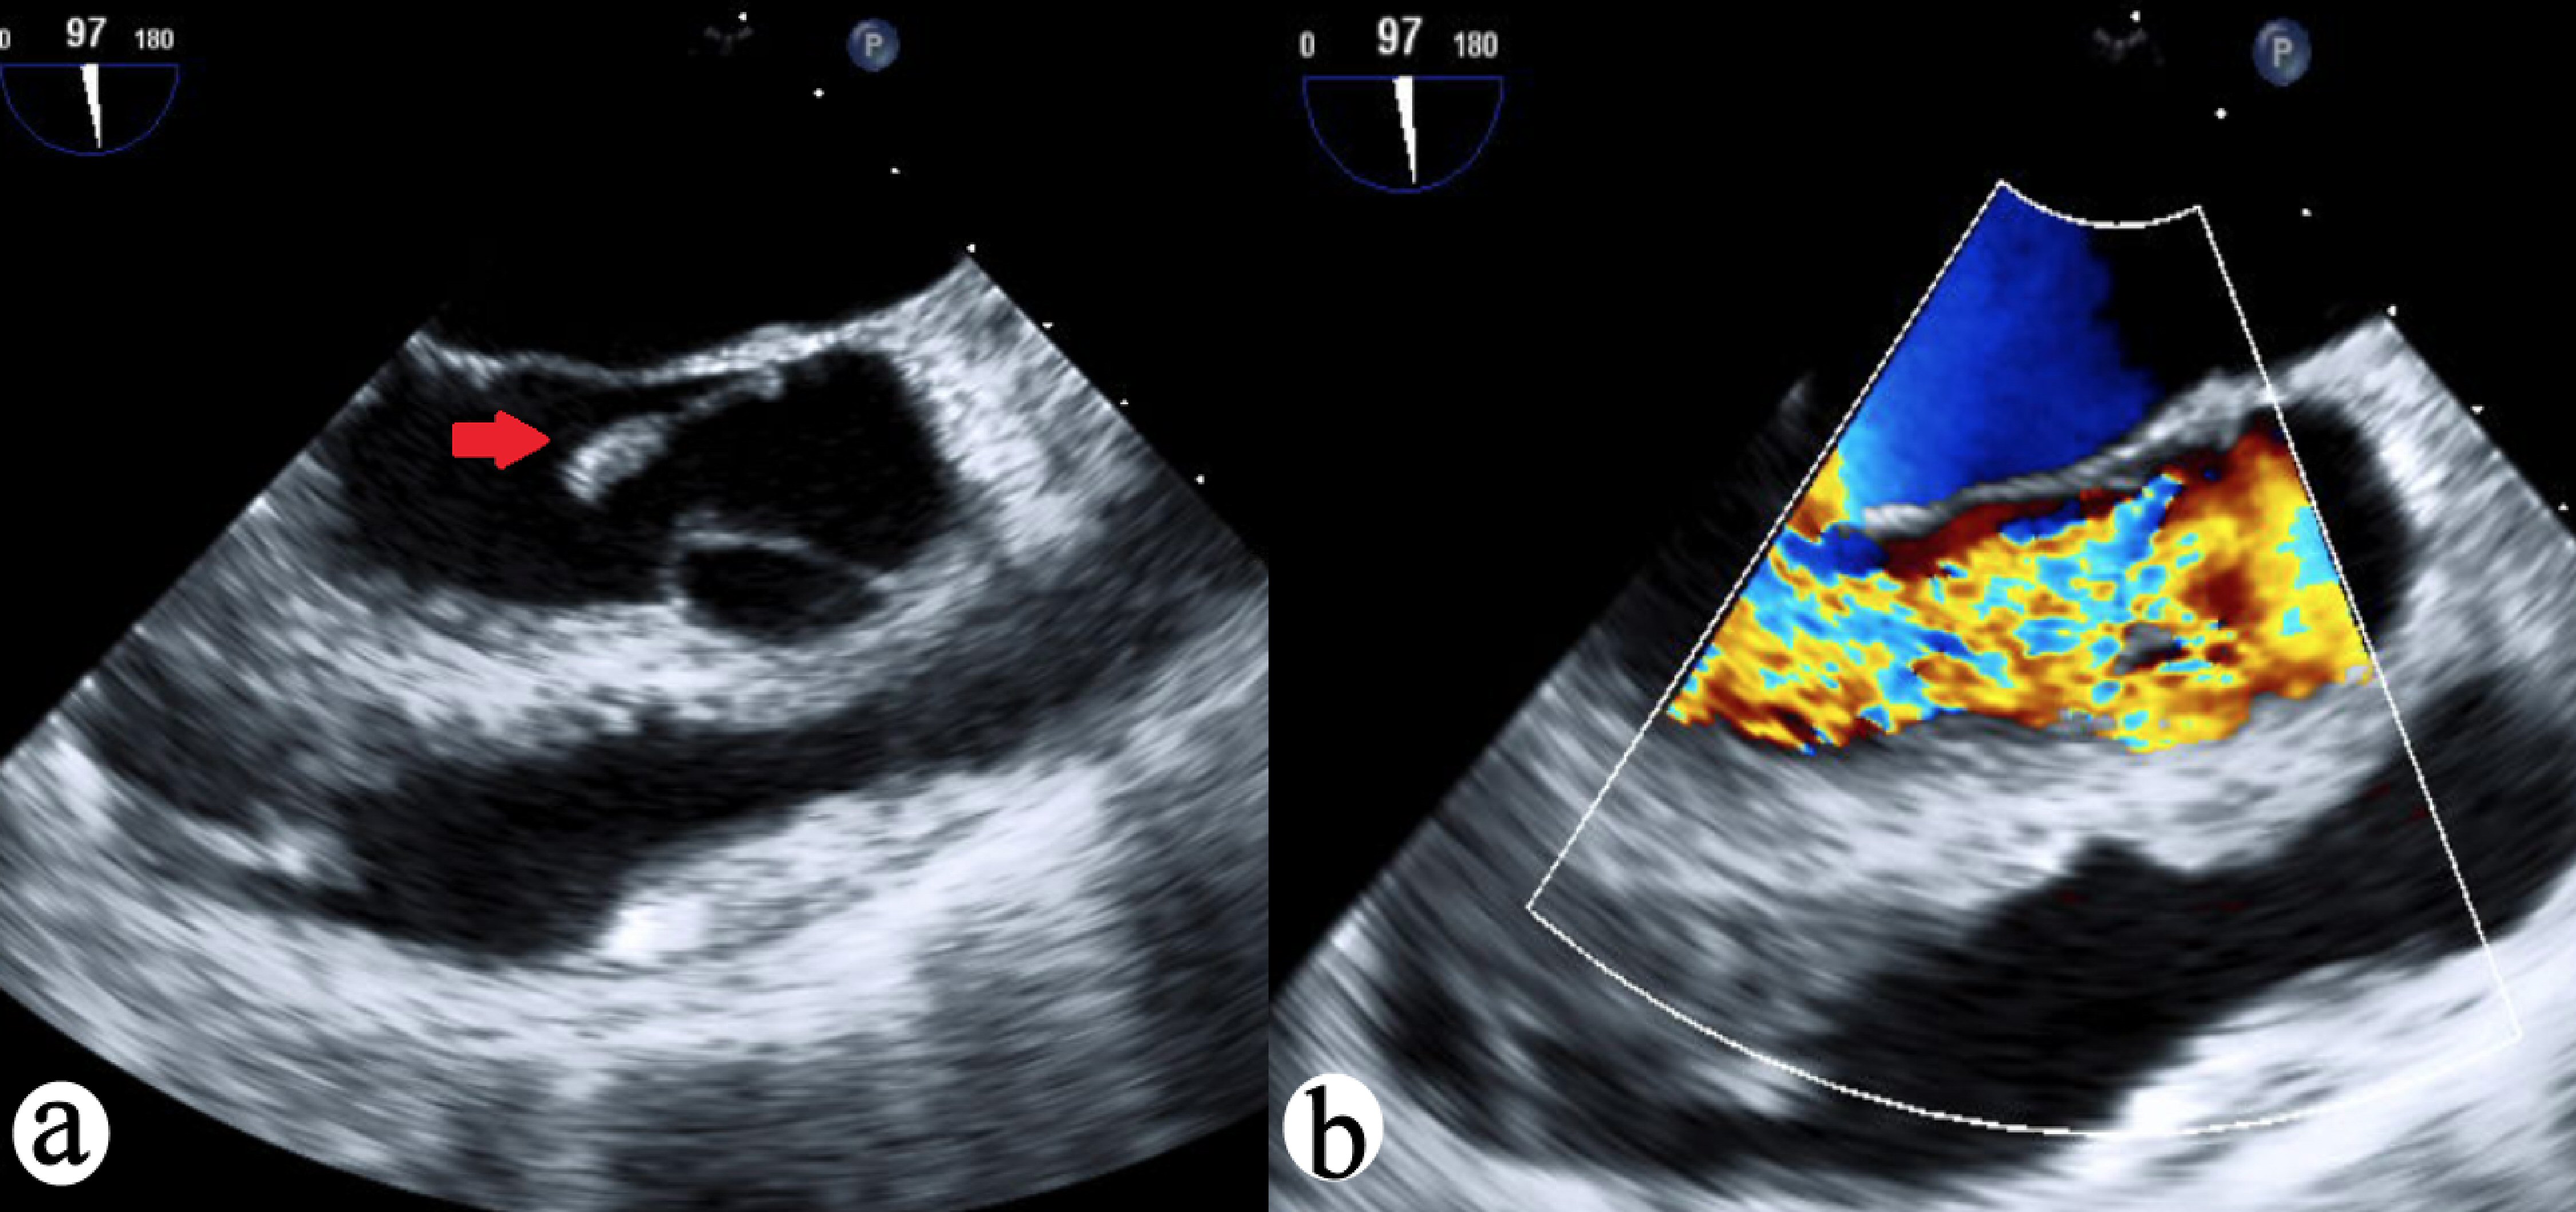

![]() Click for large image | Figure 2. (a) TEE 97-degree view of aortic valve vegetation (red arrow) with prolapse. (b) TEE 97-degree view of aortic valve with wide open aortic regurgitation. TEE: transesophageal echocardiography. |

A 31-year-old male with no significant past medical history who presented from an outlier hospital to our emergency department with an acute onset crushing substernal chest pressure and dyspnea with profuse sweating following 1-week-long febrile illness with malaise. He denied any intravenous drug use, and urine drug screen on admission was negative for illicit substance use. Initial physical exam revealed normal vital signs and clear lungs, but shortly thereafter, the patient rapidly developed dyspnea, tachypnea, and tachycardia. On vital signs patient was noted to be suddenly hypotensive and hypoxic. Neck exam exhibited elevated jugular venous distention and lungs on auscultation revealed significant crackles in bilateral lung fields. The initial electrocardiogram (ECG) showed diffuse ST depressions in all precordial leads, consistent with an acute coronary syndrome (Fig. 1). Thereafter, he underwent an emergent transthoracic echocardiogram showed ejection fraction (EF) of 45% with severe aortic insufficiency with emanating from a torn right coronary cusp, and cardiothoracic surgery consultation was procured (Fig. 2). Blood cultures came back positive for S. lugdunensis in both bottles.

Diagnosis of cardiogenic shock and flash pulmonary edema was suspected, and patient underwent rapid sequence intubation. With the consent of his family, the patient then underwent emergent transesophageal echocardiogram while intubated. This revealed a large vegetation prolapsing into the left ventricular outflow tract, confirming the diagnosis of acute severe aortic insufficiency from endocarditis (Fig. 2). While deliberating with the family about emergent aortic valve replacement, the patient suffered cardiac arrest. Advanced cardiac life support (ACLS) protocol was followed for 13 min, return of spontaneous circulation was restored and the patient was sent for emergent mechanical aortic valve replacement surgery. The native valve specimen cultures grew S. lugdunensis. The patient had a remarkably uncomplicated postoperative course and was extubated postoperative day 4, and he was neurologically intact. He was discharged home on postoperative day 8 on intravenous nafcillin to complete a 6-week course and made a full recovery without disability.